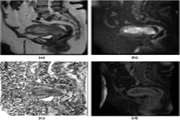

Elderberry diet improves sperm quality and histological parameters of testicular tissue in adult male rats exposed to methamphetamine 1404/01/16 - 11:04